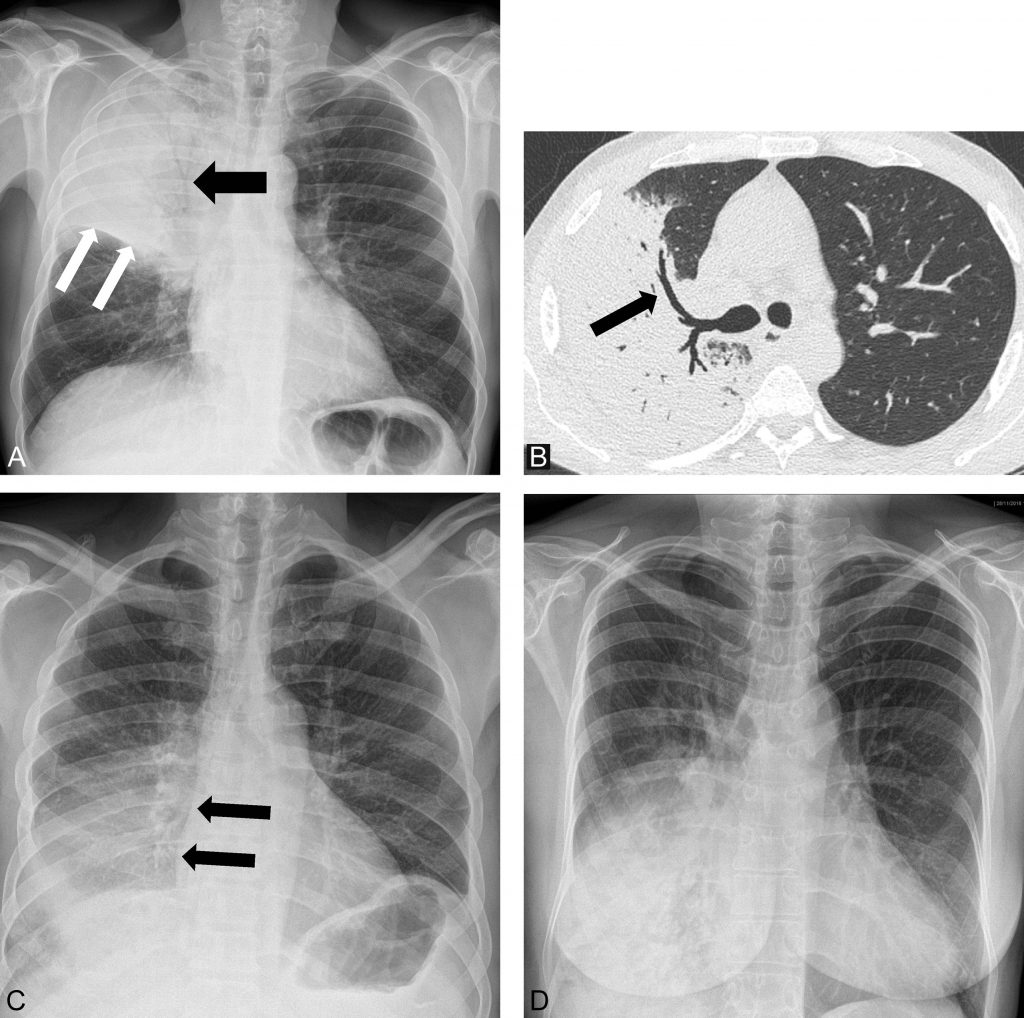

Dans le cas typique de la pneumonie franche lobaire aiguë, la radiographie thoracique montre un syndrome alvéolaire (opacité de tonalité hydrique), systématisé (à un lobe, un poumon, un ou plusieurs segments), avec un bronchogramme aérique. Le bronchogramme aérique est inconstant mais traduit la persistance d’air au sein des voies aériennes de conduction, ce qui signe l’atteinte alvéolaire (figure 96.1). Cette condensation pulmonaire ne refoule pas les structures médiastinales comme le ferait un épanchement pleural de grande abondance.

Fig. 96.1. Radiographie de thorax. Pneumonie franche lobaire aiguë.

(A) Radiographie de thorax de face. Foyer de condensation alvéolaire avec bronchogramme aérique (flèche noire), systématisé au lobe supérieur droit avec appui scissural (flèches blanches). (B) Scanner thoracique chez le même patient qu’en A. Condensation du lobe supérieur droit avec bronchogramme aérique (flèche). (C) Radiographie de thorax de face (autre patient). Foyer de condensation alvéolaire de champ pulmonaire inférieur droit, n’effaçant pas le bord droit de la silhouette cardiaque (flèches noires) . Le signe de la silhouette est négatif, la pneumonie n’est pas antérieure et intéresse donc le lobe inférieur droit. (D) Radiographie de thorax de face (autre patient). Foyer de condensation alvéolaire de champ pulmonaire inférieur droit, effaçant le bord droit de la silhouette cardiaque . Le signe de la silhouette est positif, la pneumonie est antérieure et intéresse donc le lobe moyen.

Source : CERF, CNEBMN, 2022.